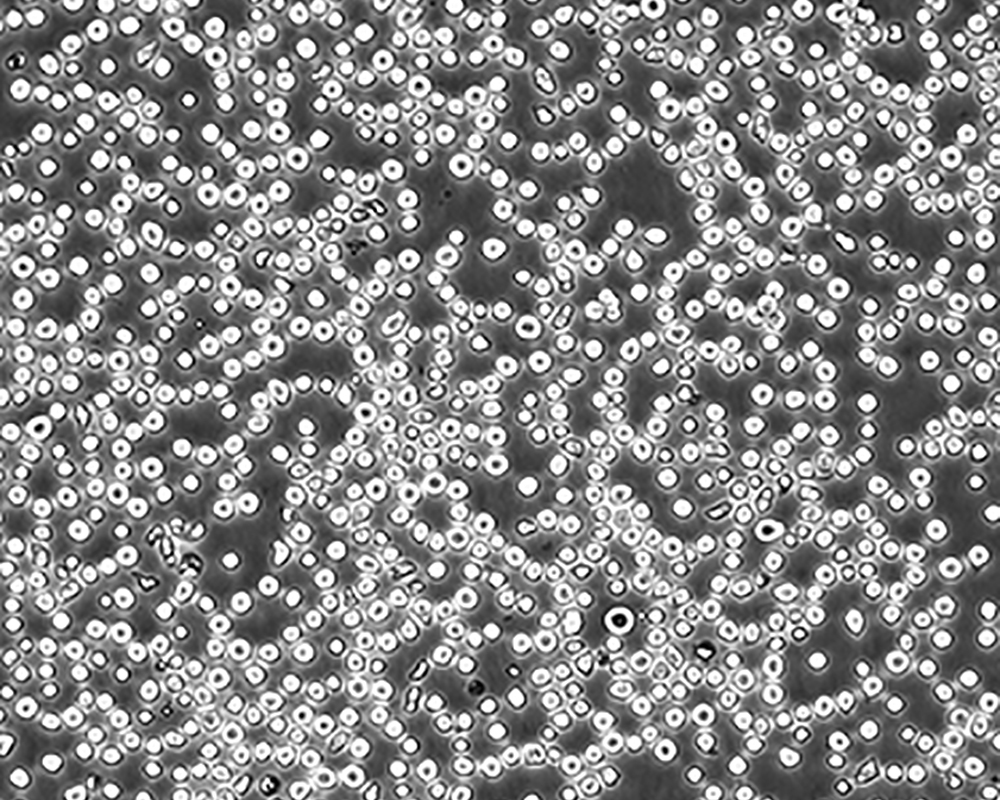

細胞描述 CEM/C1是人T細胞白血病細胞株CCRF-CEM(見ATCC CCL-119)具有喜樹堿抗性的衍生株。1991年細胞株選擇并亞克隆了對CPT的抗性。細胞表現出對CPT類似物水溶性的托泊替康和非水溶性的9-氨基-CPT及10,11-亞甲二氧基-CPT具有交叉抗性。CEM/C1細胞對CPT的敏感性較母系CEM細胞低31倍。CEM/C1細胞表現非典型的多藥抗性和轉換拓補異構酶I催化活性。對CPT的抗性維持6個月以上。